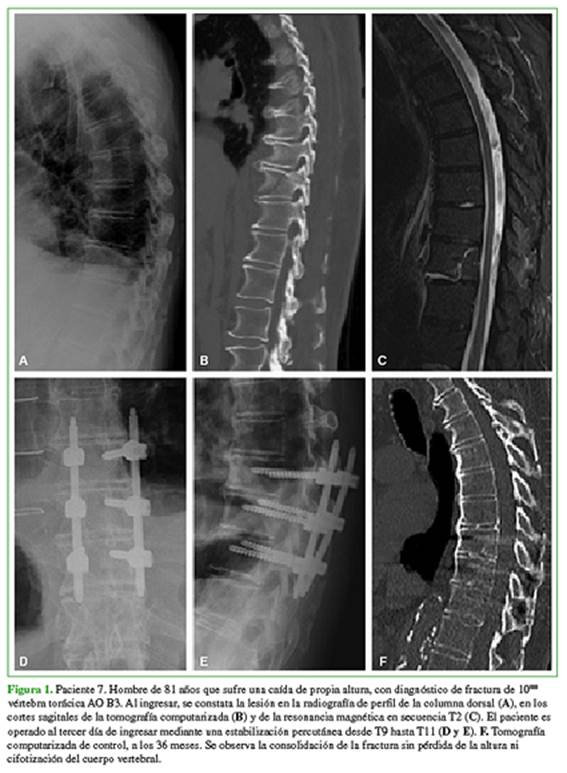

Con la aprobación previa del protocolo de investigación por parte del Comité de Ética Profesional de nuestra institución, se llevó a cabo un análisis retrospectivo de los pacientes con diagnóstico de fractura traumática de la columna toracolumbar que cumplían con los siguientes criterios de inclusión: 1) >18 años de edad en el momento de la cirugía; 2) operado entre enero de 2012 y diciembre de 2017, en nuestra institución, 3) tratado mediante sistema de fijación percutánea de manera aislada (Figura 1) o asociada a artrodesis anterior mínimamente invasiva (Figura 2), 4) un seguimiento mínimo de 6 meses.

Todas las fracturas habían consolidado en el análisis radiológico al final del seguimiento, a los 32.9 meses (rango 7-71).